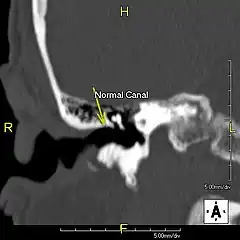

L'exostose du surfeur ou oreille de surfeur est une exostose, c'est-à-dire une croissance osseuse anormale, qui pousse vers l'intérieur du conduit auditif[1]. L'os entourant le conduit auditif réagit à l'agression thermique et mécanique de l'eau froide et de ses turbulences, par une nouvelle croissance osseuse qui a pour effet de resserrer le conduit auditif.

Du fait de la réduction du diamètre du conduit auditif, l'eau et le cérumen peuvent rester piégés entre la masse osseuse et le tympan et provoquer ainsi une infection comme une otite externe, particulièrement douloureuse.

Le contact de l’os avec le tympan peut provoquer des acouphènes[4]. Si rien n'est fait, les excroissances osseuses peuvent conduire à une obturation du conduit auditif et à une perte d'audition[1].